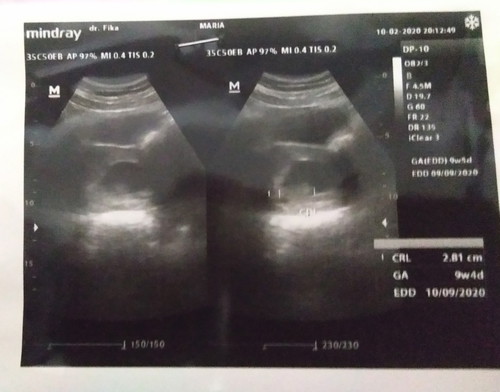

Selamat malam bunda mau tanya ini sudh ada janin nya ya

CRL itu janin bunda,